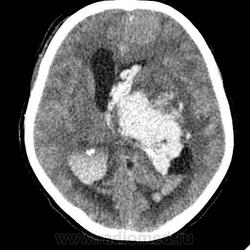

КТ головного мозга, кровоизлияние.

"Скорая" привезла женщину 75 лет, найденную на улице. На КТ направлена с д-зом: кома неясного происхождения. Вот такая картина на КТ.

Острое внутримозговое кровоизлияние с выходом крови в желудочки (боковые - сгустки преимущественно в левом + эффект седиментации с горизонтальным уровнем жидкость\жидкость в задних рогах; сгустки крови в третьем желудочке, кровь в четвертом). Значительное увеличение височных рогов боковых желудочков - гидроцефалия. Смешение срединных структур вправо, отек белого вещества перивентрикулярно слева.

Довольно большие кровоизлияния в стволе мозга (что объясняет тяжесть состояния).

Дифференциация серого и белого в-ва сохраняется, хотя субарахноидальное пространство не прослеживается - проявление масс-эффекта, начальный этап отека мозга.

Остается вопрос по слегка гиперденсному (относительно серго вещества) однородному фокусу в левой лобной доле... и по причине кровоизлияния. Что касается последнего могу предположить патологию базилярной артерии (разрыв аневризмы?)... правда не вижу что-то крови в цистернах основания черепа.

Я написала отек мозга, острое массивное (около 100 мл только внутримозговое) смешанное кровоизлияние слева + в стволе, с прорывом и гемотампонадой желудочков, выраженной латеральной дислокацией (13 мм), менингиома? лобного полюса слева. Убедительных данных за опухоль, давшую кровоизлияние, не вижу, хотя такая мысль тоже была.  Контрастировать такую пациентку никто не будет, агонизирующая(.

У, сколько всего написано. Пока не пришла Nela, поучаствую и я. 1. Кровоизлияние в ткань мозга, а не в опухоль: а)не видно ткани опухоли; б) неясна первичная локализация опухоли (левые базальные ядра?!); в)нет перифокального отека вокруг предролагаемой опухоли, г) при опухолях прорывы в желудочки - редкость; 2) к поперечной дислокации добавил бы безесловную аксиальную: даже цистерна моста сужена, не говоря уже про обходную-четверохолмную и другие; 3) менингиома в левой лобной области, на мой взгляд, сомнительна (кстати, покажите ее пожалуйста), ИМХО - "игра" плотностей;  4) ///метастазы в сосудистые сплетения/// - это очень круто, но они не дали бы внутримозгового кровоизлияния, как и ///плексуспапилома///.

PS. Не очень понял про ///отек мозга///, есть снижение плотности (отек и ишемия) белого вещества левого полушария и задних отделов правого.

Массивное медиальное кровоизлияние с прорывом в желудочки. Кровоизлияние в ствол. Признаки вклинения. В лбу может что-то и есть, но это не принципиально. А может быть и отечные извилины. Смущает, что нет масс-эффекта.

Про отек: субарахноидальных щелей совсем нет, по белому веществу и в стволе снижение плотности, извилины утолщены, серое вещество на этом фоне выглядит более светлым, толстым, подушкообразным.

Причина таких кровоизлияний, как правило, гипертензия и атеросклероз.

Кровоизлияние не связанное с объемным образованием, "гипертоническое", основной массой - в области базальных ядер, кровоизлияние в ствол мозга, кома ясного происхождения :) А менингиома менигниомой, не мешает, так сказать.  Отека мозга здесь небольшой, больше выражено набухание.